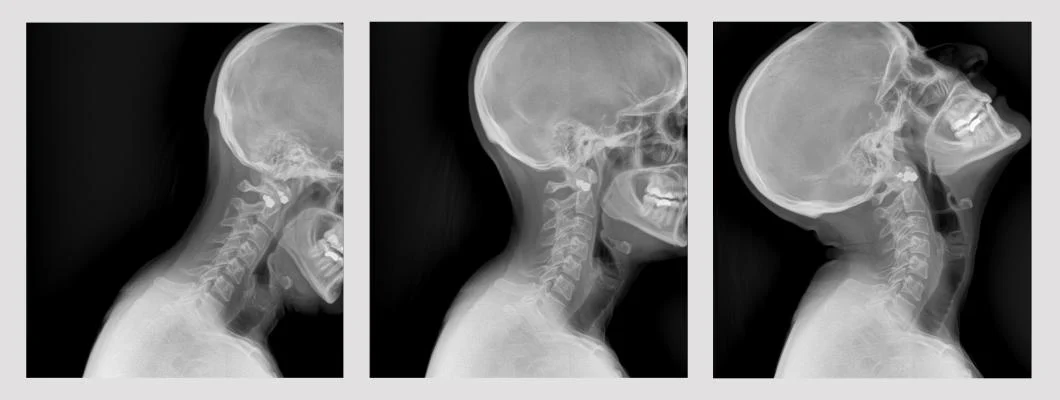

DDR — это следующая эволюция рентгеновских лучей, позволяющая клиницистам наблюдать за динамическим взаимодействием анатомических структур, таких как ткани и кости, с физиологическими изменениями с течением времени. В отличие от рентгеноскопии, DDR представляет собой серию отдельных цифровых рентгеновских изображений, полученных с высокой скоростью и низкой дозой облучения, что позволяет визуализировать анатомию в движении. В одном и том же исследовании клиницисты могут получать статические и динамические изображения. DDR широко используется в различных областях клинической медицины, включая исследование легких, опорно-двигательного аппарата, трансплантацию легких, исследования глотания и т. д., и используется как для контрастных, так и для бесконтрастных исследований.